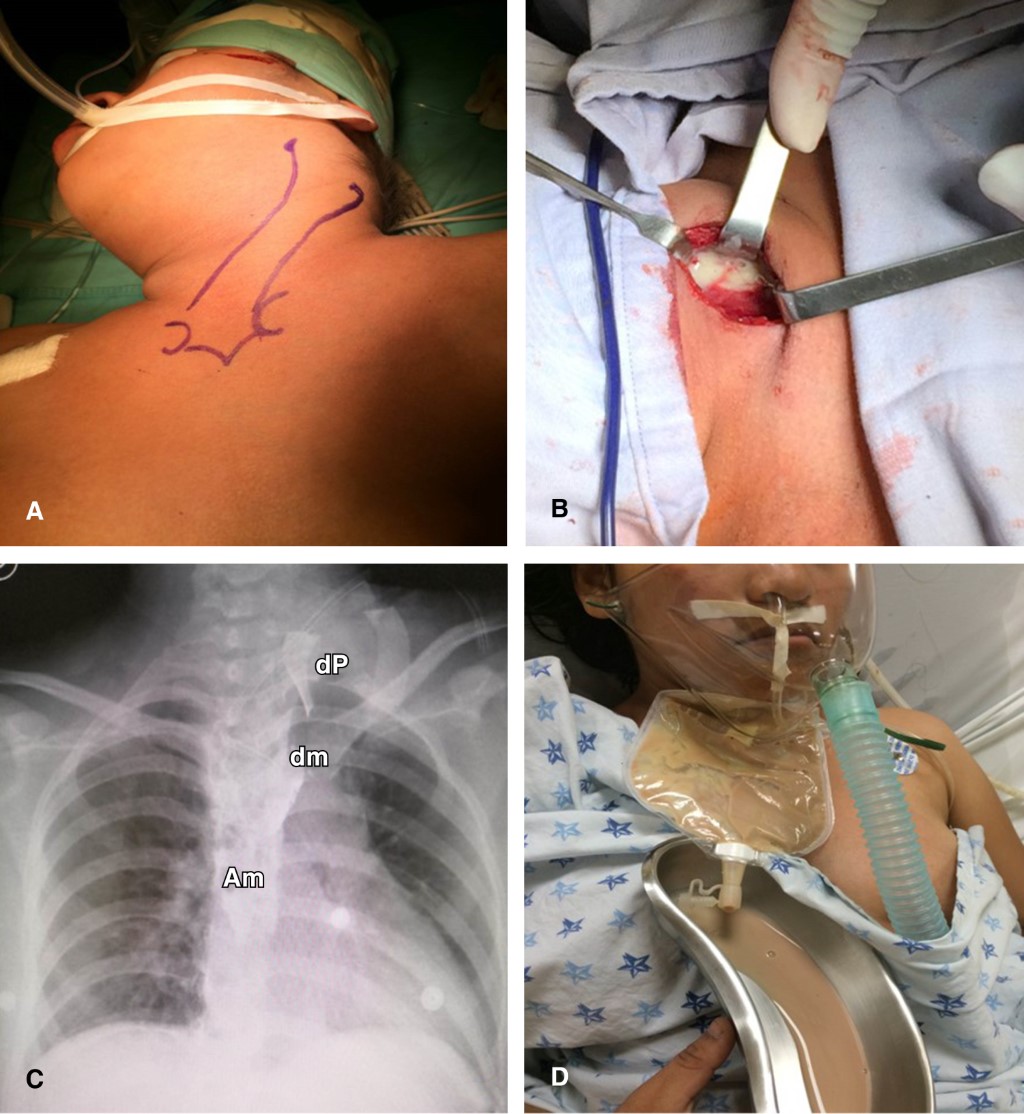

Por considerar la vía transendoscópica insuficiente para el drenaje de la cavidad mediastinal septada se lleva a cabo un abordaje cervical posterior izquierdo convencional que permitió un desbridamiento mecánico e irrigación exhaustiva con solución fisiológica salina de todo el absceso cervicomediastinal de 500 mL de material purulento. No fue posible el cierre primario de la perforación de 2 cm por la excesiva respuesta fibrótica y bordes faringoesofágicos necróticos con mala irrigación. Se colocó un drenaje cervical de Penrose simple y otro drenaje dual para irrigación-drenaje hacia la cavidad del absceso mediastinal. En el mismo tiempo quirúrgico se ejecutó una gastrostomía con funduplicatura antirreflujo para apoyar la rehabilitación esofágica y nutricional futuras. Inició ayuno con nutrición parenteral por cinco días, antibióticos con ceftriaxona y clindamicina por 21 días e irrigación diaria de la sonda dual mediastinal con mejoría clínica (Figura 4).

Con dos semanas de irrigación y drenaje se eliminó el gasto purulento, se retiró la sonda dual dirigida a mediastino y se corroboró la involución del absceso en la tomografía. Al persistir el trayecto fistuloso faringocutáneo con gasto de saliva como una verdadera esofagostomía cervical (en el tracto del drenaje de Penrose simple) se realizó nueva endoscopia digestiva superior con paso a estómago sin estenosis residuales y con la presencia de un doble trayecto fistuloso: uno faringocutáneo comunicado al exterior largo y otro faringomediastinal comunicado al interior del mediastino corto de 2 cm. La cavidad mediastinal con tendencia hacia la obliteración por tejido de granulación permitió instilar por vía endoscópica a través del canal de trabajo con un catéter de 3 French una solución de cianoacrilato 10 mL como adhesivo tisular en el interior de todo el doble trayecto fistuloso, disminuyendo notablemente el gasto de saliva por la fístula faringocutánea hasta su cierre completo una semana después. En la evolución posterior no hubo disfagia, tolerando la vía oral, y control con serie esofagogastroduodenal sin secuelas ni complicaciones (Figura 5).